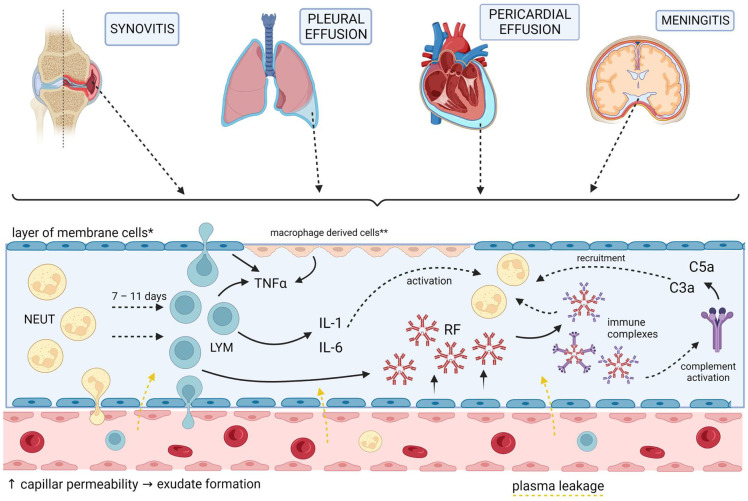

Arthritic changes – Arthritis is related to a condition of painful joints due to inflammation or swelling. A type of arthritis is rheumatoid arthritis, it is an autoimmune disease where the immune system attacks the joints, starting with the lining of joints. Rheumatoid arthritis is heavily related to lung problems, about 80% of arthritic patients have lung-related issues, making it the second leading cause of death with rheumatoid arthritis patients. Rheumatoid arthritis caused lung problems are most commonly extra-articular i.e., outside of the joints and involves pulmonary nodules; damage to the lung airways, pleural effusion and interstitial lung disease. In rheumatoid arthritis associated interstitial lung disease the auto-immune system gets over active and attacks the lungs and causes scarring. With time, the scarring build-up leads to difficulty breathing and reduced lung function.

pleuritic pain– is caused during pleurisy, a condition of inflamed pleura caused by a variety of virus or bacterial or other illnesses that travels to the pleurae. The pleuritic chest pain can be defined as a sharp pains that gets worse during inspiration or expiration. Apart from the bacterial or viral infections, pleurisy can also be caused by autoimmune diseases (lupus), pleural disease (i.e., mesothelioma), chest trauma, sickle cell disease, IBD, pulmonary embolism and certain medications etc. (can make an image using bio-render)